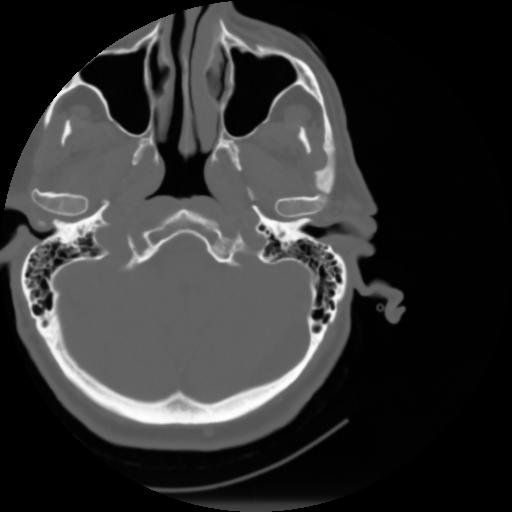

3 CEREBRO,,Axial,3.0,CEREBRO,,